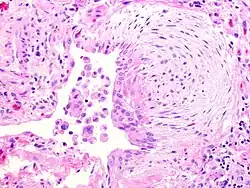

![]() | Fibroblasts | Fibroblasts in intestinal pneumonia | Category: Fibroblasts | Fibroblast |